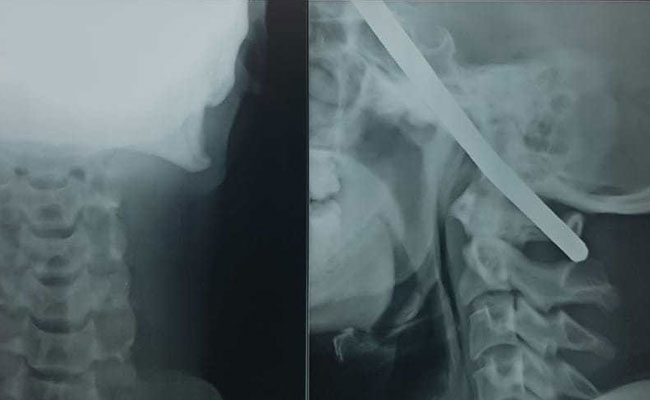

15-Inch Rod Pierces Man's Head, He Survives After 10-Hour-Long Surgery

A Chinese man miraculously survived after a 15-inch metal rod went through his mouth into his head. The tragic incident occurred when he was having dinner with co-workers at a restaurant.